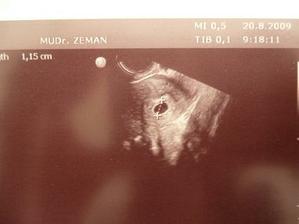

20.8. potvrzeno těhotenství doktorem, jsem v 5 - 6 tt